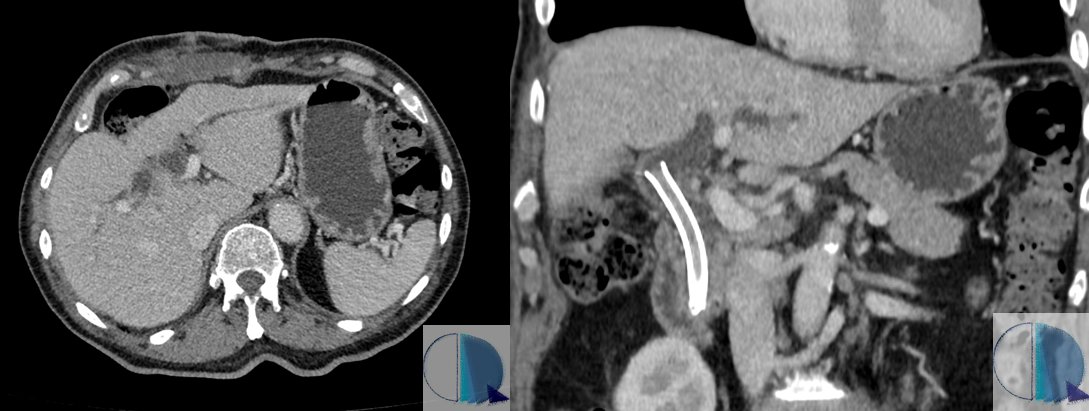

Hey there! Let´s get some #YesSpectralCCT for this friday at RM y TC Rosario. This is the case of a 53yo patient who underwent a body CT for follow-up of colon cancer and unknown atrial fibrillation. The study was unremarkable, except for this finding. 1/8

Hey there! Let´s get some #YesSpectralCCT for this friday at <a href="/RMyTC_Rosario/">RM y TC Rosario</a>. This is the case of a 53yo patient who underwent a body CT for follow-up of colon cancer and unknown atrial fibrillation. The study was unremarkable, except for this finding.

1/8